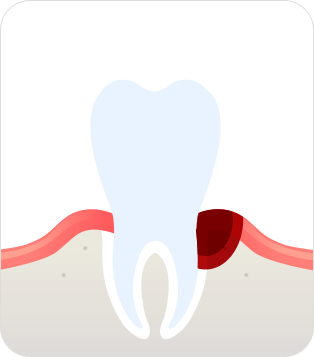

치은염(초기 ~중기)

잇몸이 붓거나 치아가 시린 등의

염증이 잇몸에만 나타남